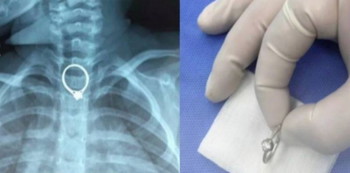

Reports say that the two-year-old had asked to play with the ring. Shortly after her mom had fallen asleep, the toddler started to cry, pointing to her mouth to say she had swallowed the ring.

Her worried mom rushed her to the Zhuhai Hospital of Integrated Traditional Chinese and Western Medicine. Doctors at the hospital managed to fish out the ring, which measured 2.35cm by 2.05cm, after a 30-minute operation.